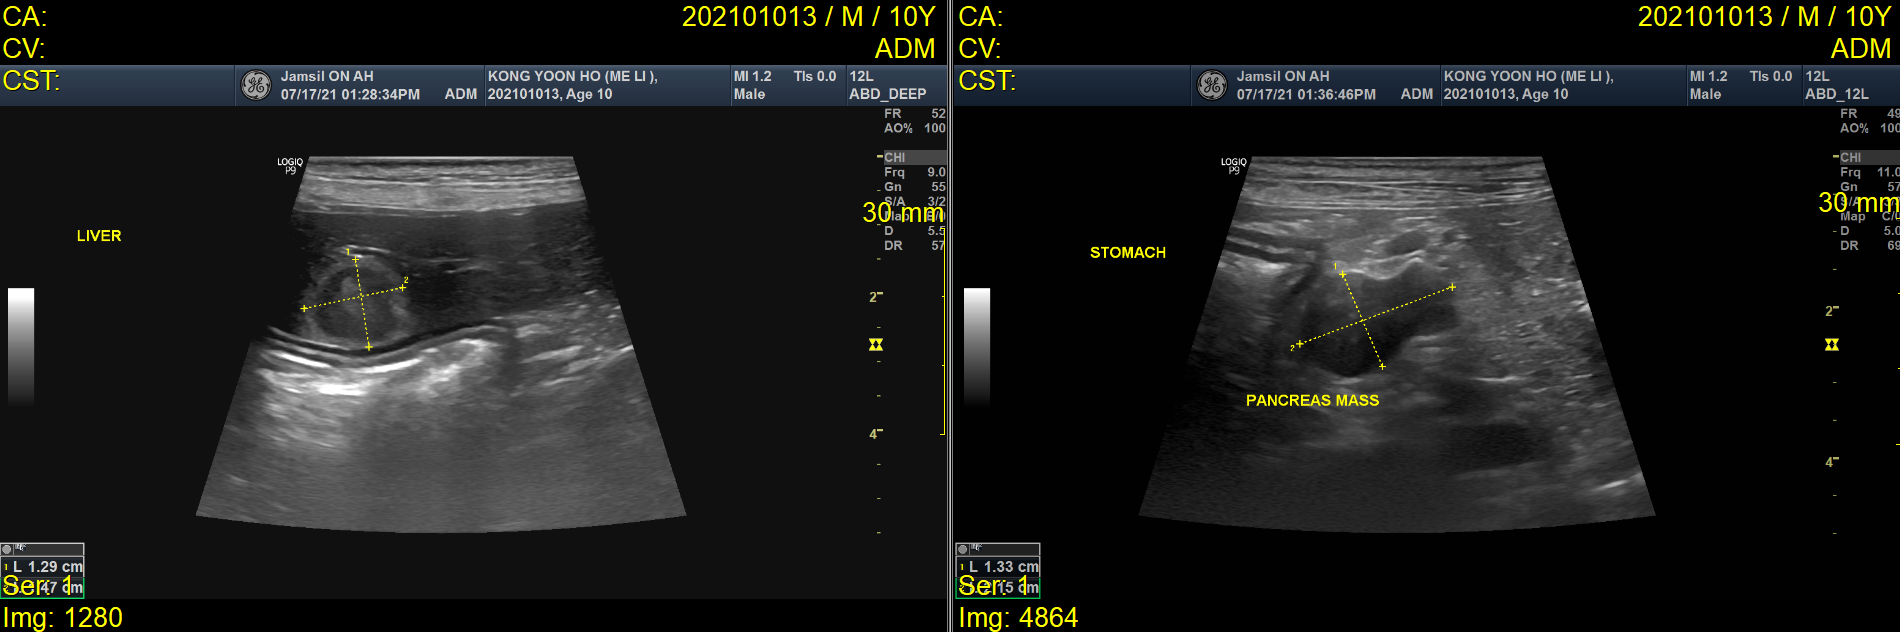

<메리의 CT사진>

또, 초음파와 CT검사를 통해 간과 비장, 췌장에 림프절이 커져있음을 확인하였습니다.

이는 주변 조직 전이를 의미하는 소견으로, 보호자님과 상의하에 추가적인 조직검사까지 진행하지는 않았습니다.

잠실ON동물의료센터에서는 이러한 여러 소견을 바탕으로 인슐린종(Insulinoma)로 잠정 진단하였으며 이에 대한 치료, 관리를 하기로 결정했습니다. 메리의 케이스는 여러 장기로의 전이가 의심되는 상황이었어요..